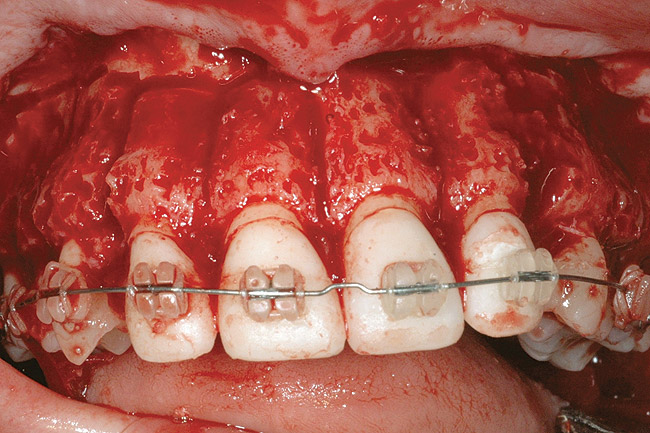

Fig 4. Note gingival inflammation caused by biologic width violation. Provisional restorations were placed on Nos. 6, 8, 9, and 11, and corticotomies were performed from Nos. 3 to 14.

Figure 4